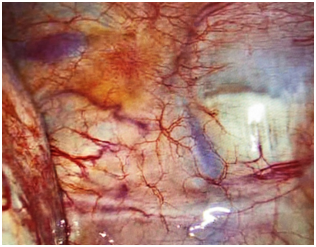

The patient underwent robotic single-incision laparoscopic surgery (SILS) resection of endometriosis, ovarian cystectomy, lysis of adhesions, and cystoscopy by Minimally Invasive Gynecologic Surgery (MIGS) team. After completion of the patient’s pelvic surgery, the thoracic surgery team performed bilateral video-assisted laparoscopy surgery (VATS) with assistance from the MIGS to help identify suspicious lesions. Intraoperative evaluation revealed thoracic endometriosis confined to the pleura of the lungs and the diaphragm. These lesions were resected via electrocautery (Figures 1–3). No parenchymal lung lesions were identified. The patient had an uncomplicated recovery and postoperative phase. Upon discharge the patient was started on oral contraceptive pills (OCPs). Based on the clinical presentation and intraoperative findings the patient was diagnosed with thoracic endometriosis.

Figure 1 Endometriosis of the right ovary.